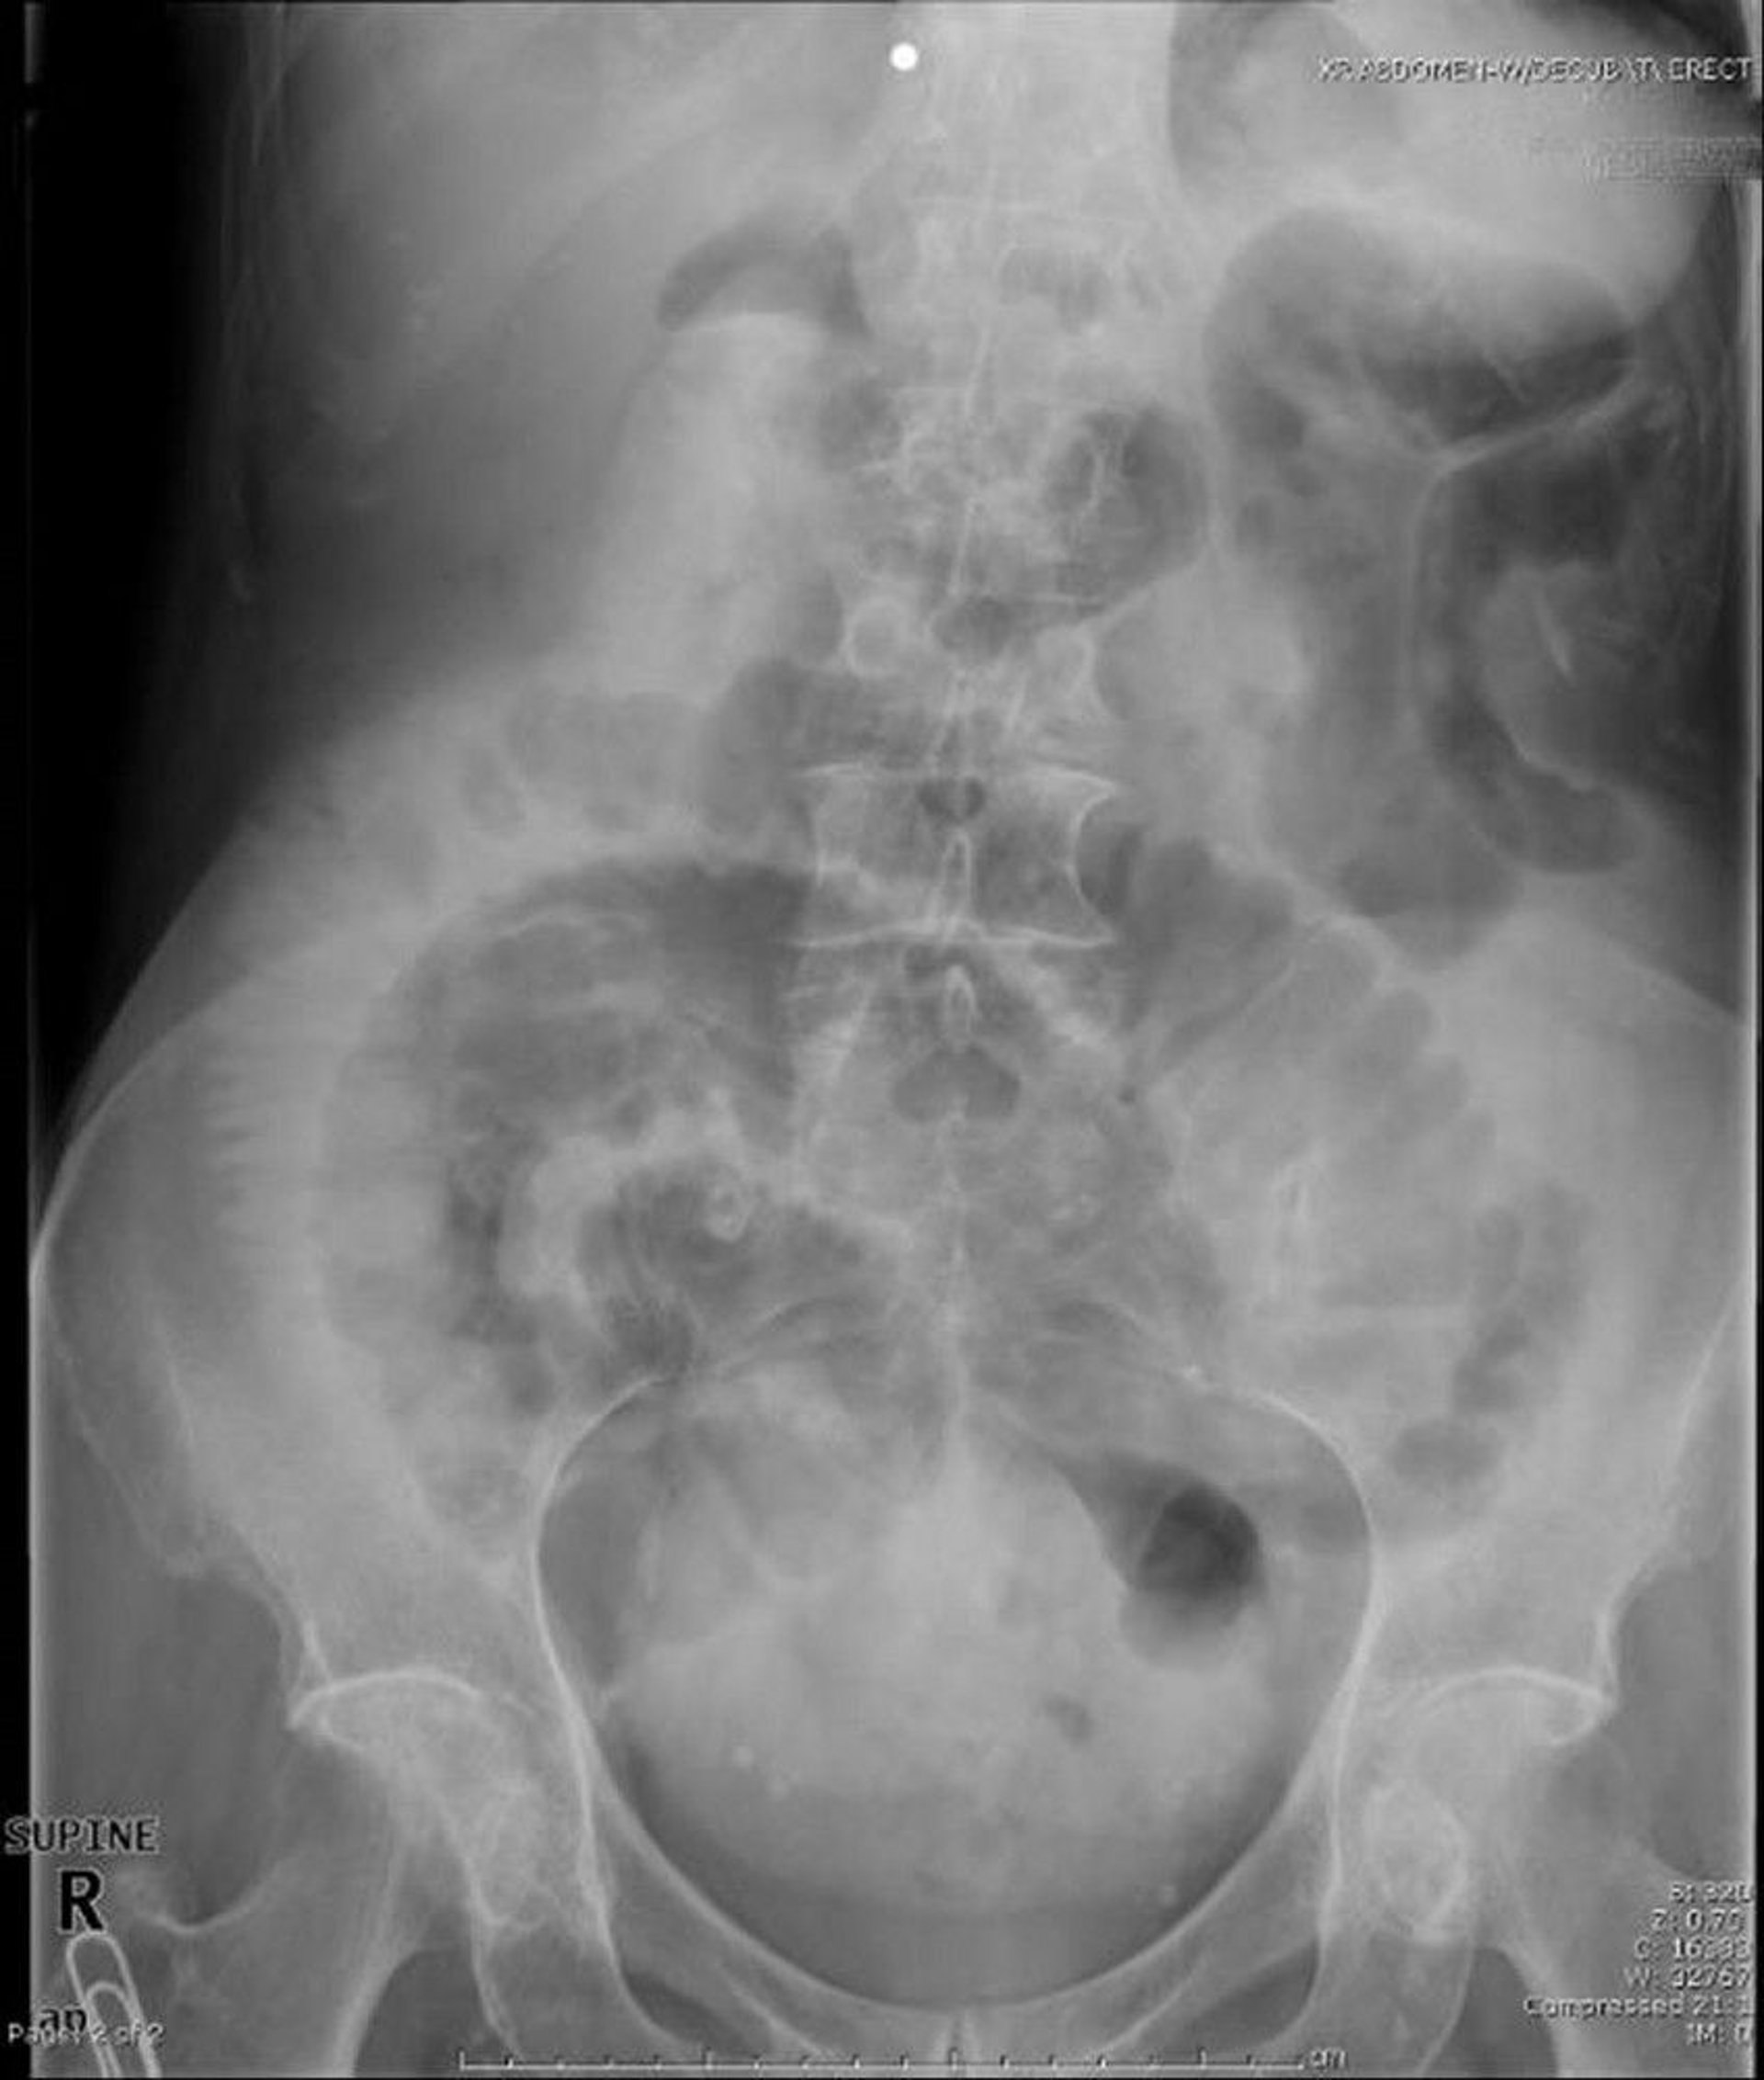

Small-Bowel Obstruction (Supine Radiograph)

This supine abdominal radiograph shows obstruction of the small bowel. Note the dilated loops of small bowel.

Image provided by Parswa Ansari, MD.